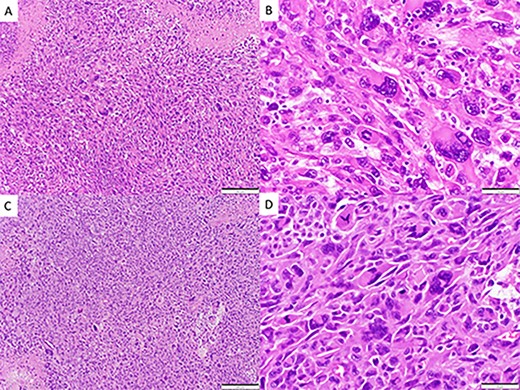

CASE

Spindle cell neoplasm with pleomorphic epithelioid features, multinucleation, mitoses and necrosis, involving pulmonary artery (A, B) and brain (C, D), H&E.